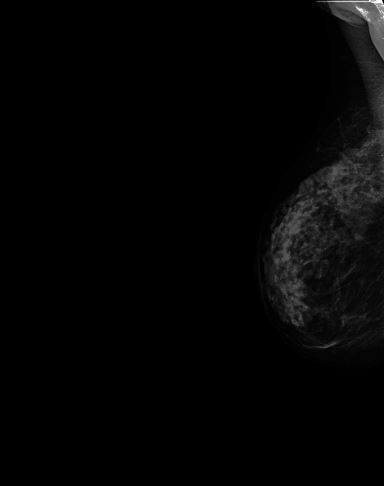

A Glimpse of CAD Functionalities On Preloaded Real Digital Mammograms

Raw Mammogram

Figure (2)

Raw digital mammography MLO view